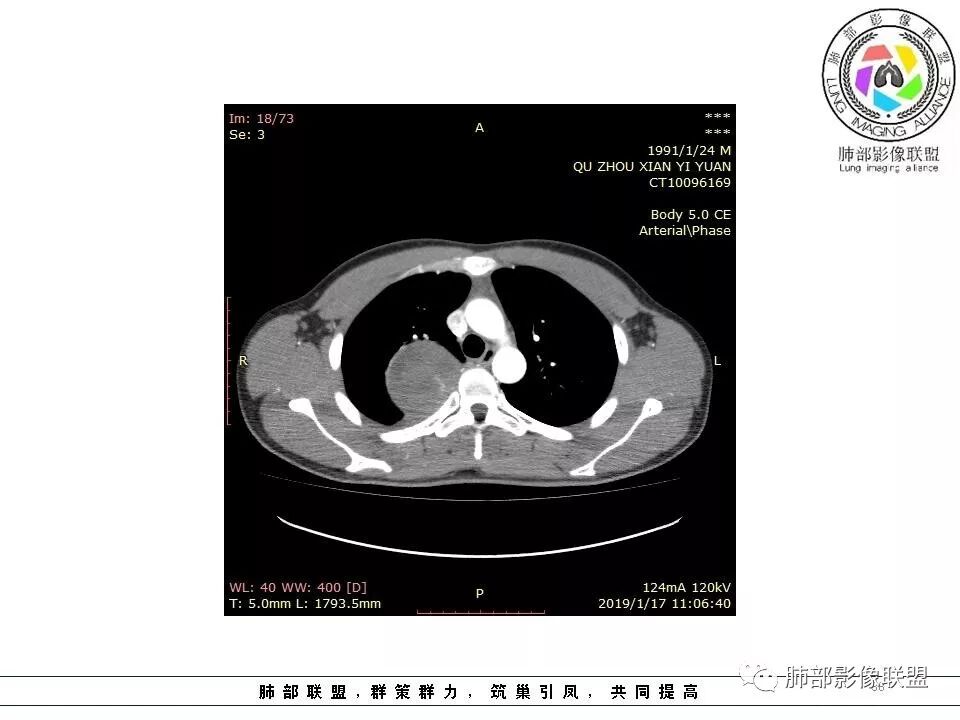

后纵隔脊柱旁占位性病变,疾病谱有神经鞘瘤,sft,节细胞瘤,髓外造血。此例有胸膜尾征,蛇纹征 ,延迟强化。考虑胸膜孤立性纤维瘤。看到有供血动脉,但不知道是哪里的血管。

后纵隔类圆形新生物,边缘光滑,胸膜尾征明显,贴近脊柱,蛇纹,血供丰富,考虑后纵隔软组织肿瘤,具体类型看不出来,鉴别神经鞘瘤。

右侧后纵隔脊柱旁占位,边缘光滑清晰,内侧肺组织受压,外侧可见胸膜尾征,增强持续强化,并可见蛇纹血管征。考虑SFT

右肺占位,跨越上叶后段、下叶背,边缘光滑,瘤肺界面清,见肺压缩缘(线样不张`强化),见胸膜尾征,胸膜下脂肪未见明显增厚,肋骨丶脊柱未见侵袭及受压,渐进性丶地图样强化,冠状位似见体循环供血

诊断:SFT(来源壁层胸膜?一般小于20%)

右后纵膈肿块,肺瘤界面清楚,胸膜尾征,邻近肺组织及支气管被推移,部分脂肪间隙存在,定位肺外来源,血供来自肋间动脉,增强后持续渐进强化,蛇纹征,考虑SFT,鞘瘤肿块内血管罕见,不考虑。

右上肺野脊柱旁软组织肿块,边缘光滑整齐,肺组织及气管右肺上叶支气管受压前移,外移,边缘可见胸膜尾征,病灶内密度不均,增强后渐进性持续强化,其内可见明显蛇纹血管征,首先考虑肺外来源,sft.可能性大